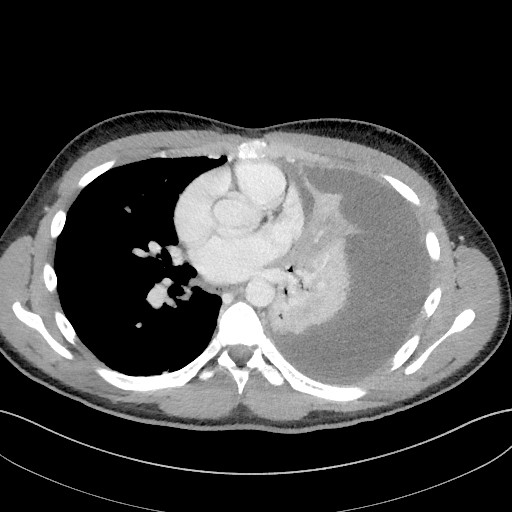

A week later, his general condition was still good, but he became increasingly hypoxic with oxygen saturation down to 90 %. Despite seven days of intravenous cefotaxime treatment, his CRP was 199 mg/l. A chest CT scan revealed that almost the entire left thoracic cavity was filled with expansionary pleural fluid and findings were consistent with pneumonia in the adjacent atelectatic left lower lobe (Fig. 1).

Figure 1 Axial CT images of the chest obtained one week after hospitalisation revealed that almost the entire left thoracic cavity was filled with expansionary pleural fluid which the radiologist interpreted as due to infection